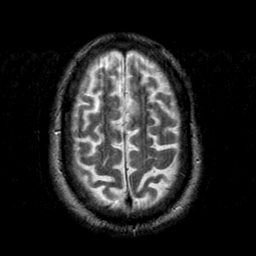

Subacute Stroke overlay -- Slice #19

[Home][Help][Clinical] Slice 19